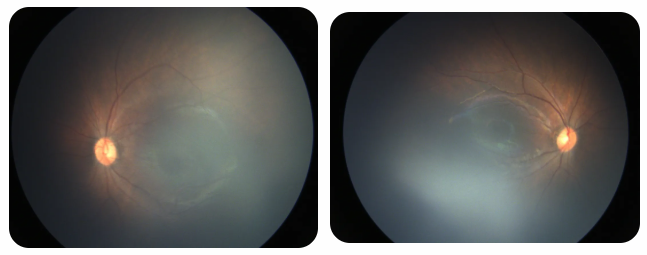

廈門眼科中心黎曉新名醫(yī)工作室曾接診一名31周出生的早產(chǎn)兒,出生體重僅1300克。由于家長(zhǎng)缺乏篩查意識(shí),直到孩子5個(gè)月大時(shí)眼睛仍不會(huì)追光,才前來(lái)就診。檢查發(fā)現(xiàn),患兒ROP已進(jìn)展至4B期,因纖維血管增殖牽拉導(dǎo)致視網(wǎng)膜脫離,錯(cuò)過(guò)了最佳治療窗口。盡管黎曉新教授團(tuán)隊(duì)成功實(shí)施了玻璃體切割手術(shù),孩子的視力仍存在不可逆損傷。此后,孩子開(kāi)啟了長(zhǎng)期隨診復(fù)查、治療的“護(hù)眼征程”,目前其右眼矯正視力為0.6,左眼為0.8。

近期術(shù)前檢查:

早產(chǎn)兒視網(wǎng)膜病變

術(shù)后復(fù)查:

相比之下,另一位早產(chǎn)寶寶在出生5周后,生命體征穩(wěn)定之時(shí),便在產(chǎn)科醫(yī)生的建議下轉(zhuǎn)診至廈門眼科中心。經(jīng)篩查確診為Ⅲ期ROP,黎曉新教授團(tuán)隊(duì)及時(shí)為其進(jìn)行了激光治療。半年后復(fù)查顯示,寶寶的視網(wǎng)膜血管發(fā)育正常,視力發(fā)育與足月兒童無(wú)異。